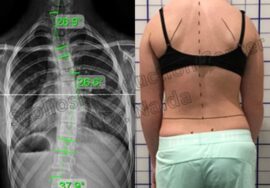

ثانيًا: أهمية قياس زاوية كوب (Cobb Angle)

تُعتبر زاوية كوب هي الطريقة العالمية الأساسية لقياس درجة اعوجاج العمود الفقري.

📌 كلما زادت الزاوية، زادت شدة الحالة.

قياس زاوية كوب

👉 بشكل مبسط:

- 10 إلى 24 درجة: اعوجاج بسيط

- 25 إلى 49 درجة: اعوجاج متوسط

- 50 درجة فأكثر: اعوجاج شديد

ومن المهم أن نفهم أن هذه الزاوية ليست رقمًا فقط، بل تساعد الطبيب على تحديد خطة العلاج المناسبة بدقة. لذلك، فإنها عنصر أساسي في متابعة الحالة.